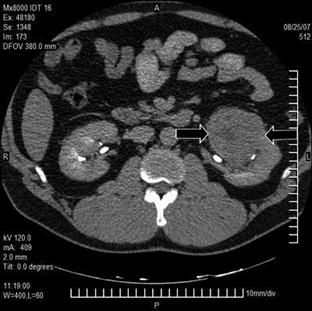

Понимание кавернозного туберкулеза почки

Раздел: Мудрость в деталях